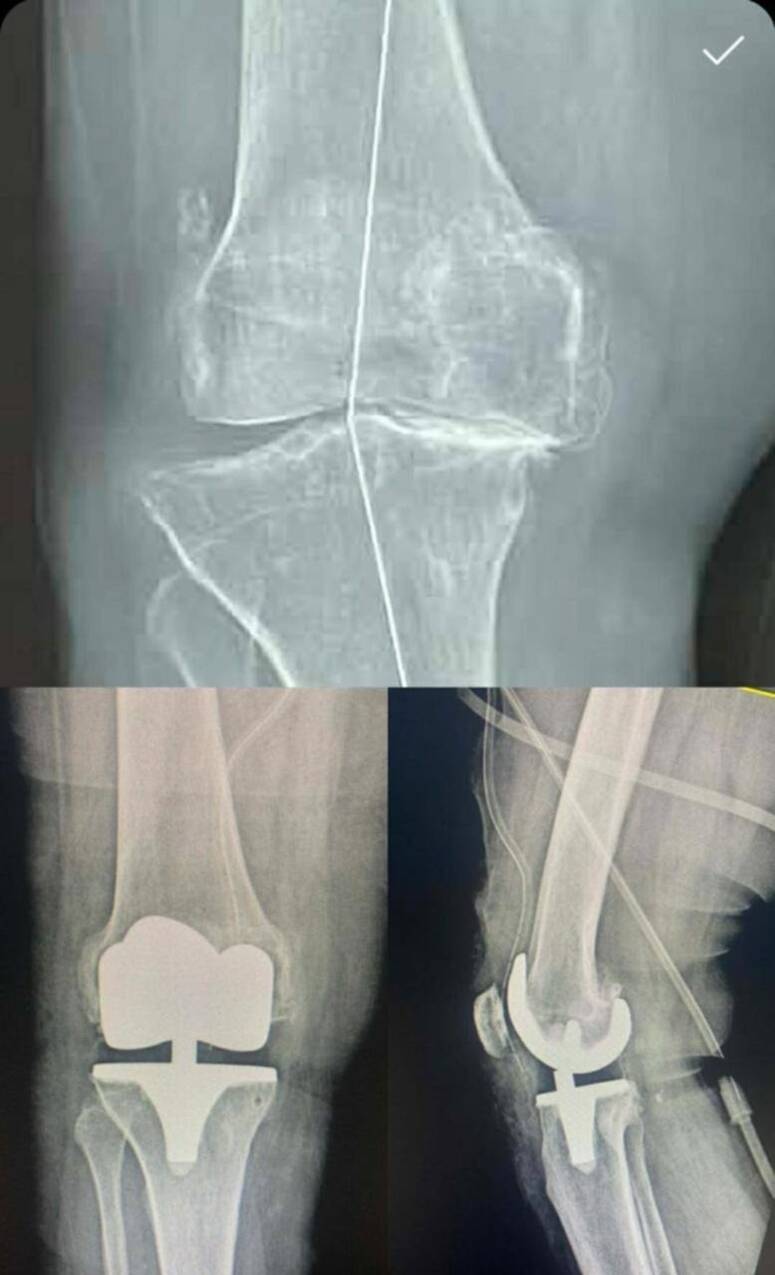

جندوبة: نجاح أوّل عملية تركيب مفصل اصطناعي كامل بالمستشفى الجهوي بجندوبة

نجح فريق طبي بالمستشفى الجهوي بجندوبة، أمس الجمعة، في إجراء أول عملية جراحية دقيقة لتركيب مفصل اصطناعي كامل للركبة بالمؤسسة، لفائدة مريض يعاني من داء مفصل الركبة في مرحلة متقدمة (الفصال العظمي الشديد).